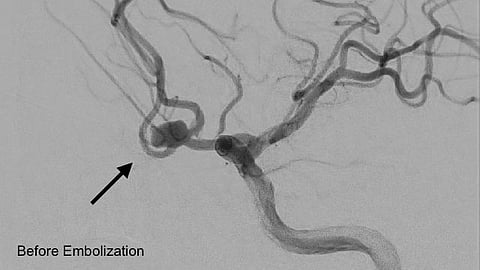

ونُفِّذ الإجراء بواسطة فريق التدخلات العصبية باستخدام ملفات معدنية دقيقة لإغلاق التمدد الشرياني، ما أسهم في السيطرة الكاملة على النزيف واستقرار حالة المريض واستعادته وعيه بالكامل.